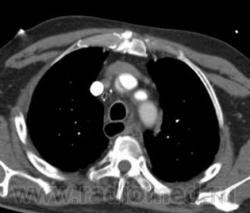

Рассоение аорты тип "A". Восходящий, нисходящий отдел, дуга, переход на брахиоцефалы...

Согласна. Только насчет брахиоцефала возражаю. Его не видно. То, что на 2 срезе, может оказаться верхней точкой дуги аорты. Нужны еще реконструкции, фронтальные например или весь объем.

Здраствуйте,я новый участник, и только начинающий врач- но у меня уже был один такой случаий- по моему это аневризма аорты с расслоением.Если бы вы прошли до бифуркации аорты -и там тоже увидели аневризму с расслоение то можно было бы поставить диагноз- аневризма с расслоением по Де Бейки- 1 тип.А какая опереция на сердце?

Ага, я видно поторопилась. Когда я писала, были только аксиалы и то не все. Теперь, когда появились фронтальные реконструкции вижу переход на устье плечеголовного ствола. Есть признаки разрыва: жидкость в плевральной полости и немного в легком.

Да, есть.

Вопрос легкий, но все же задам: предположим, что контрастирование одинаковое обеих поосветов - какой из них будет ложным , и почему ( на примере данного случая: ложный просвет тот котороый законтрастирован ярче или тот который темнее?). Указываете ли вы это в своем описании?

Ну, в данном случае понятно, что просвет который законтрастирован слабее - является ложным. Но в некоторых случаях, довольно сложно определить истинный и ложный просвет. В этом могут помочь: 1. Истинный просвет обычно меньше на аксиалах 2. СимПтом 'клюва' или 'beak sign" - наиболее характерный признак для ложного прросвета ( четко представлен в данном случае)то есть есть клювообразные выпячивания по периферии ложного просета в сторону истинного. 3. Cobweb sign - тоже характерен для ложного просвета ( мелкие 'ниточки' от отслоенной интимы в сторону ложного просвета. Другие признаки менее специфичны Доольно сложно иногда бывает отличить где исинный а где ложный просвет прихронических аневризмах.